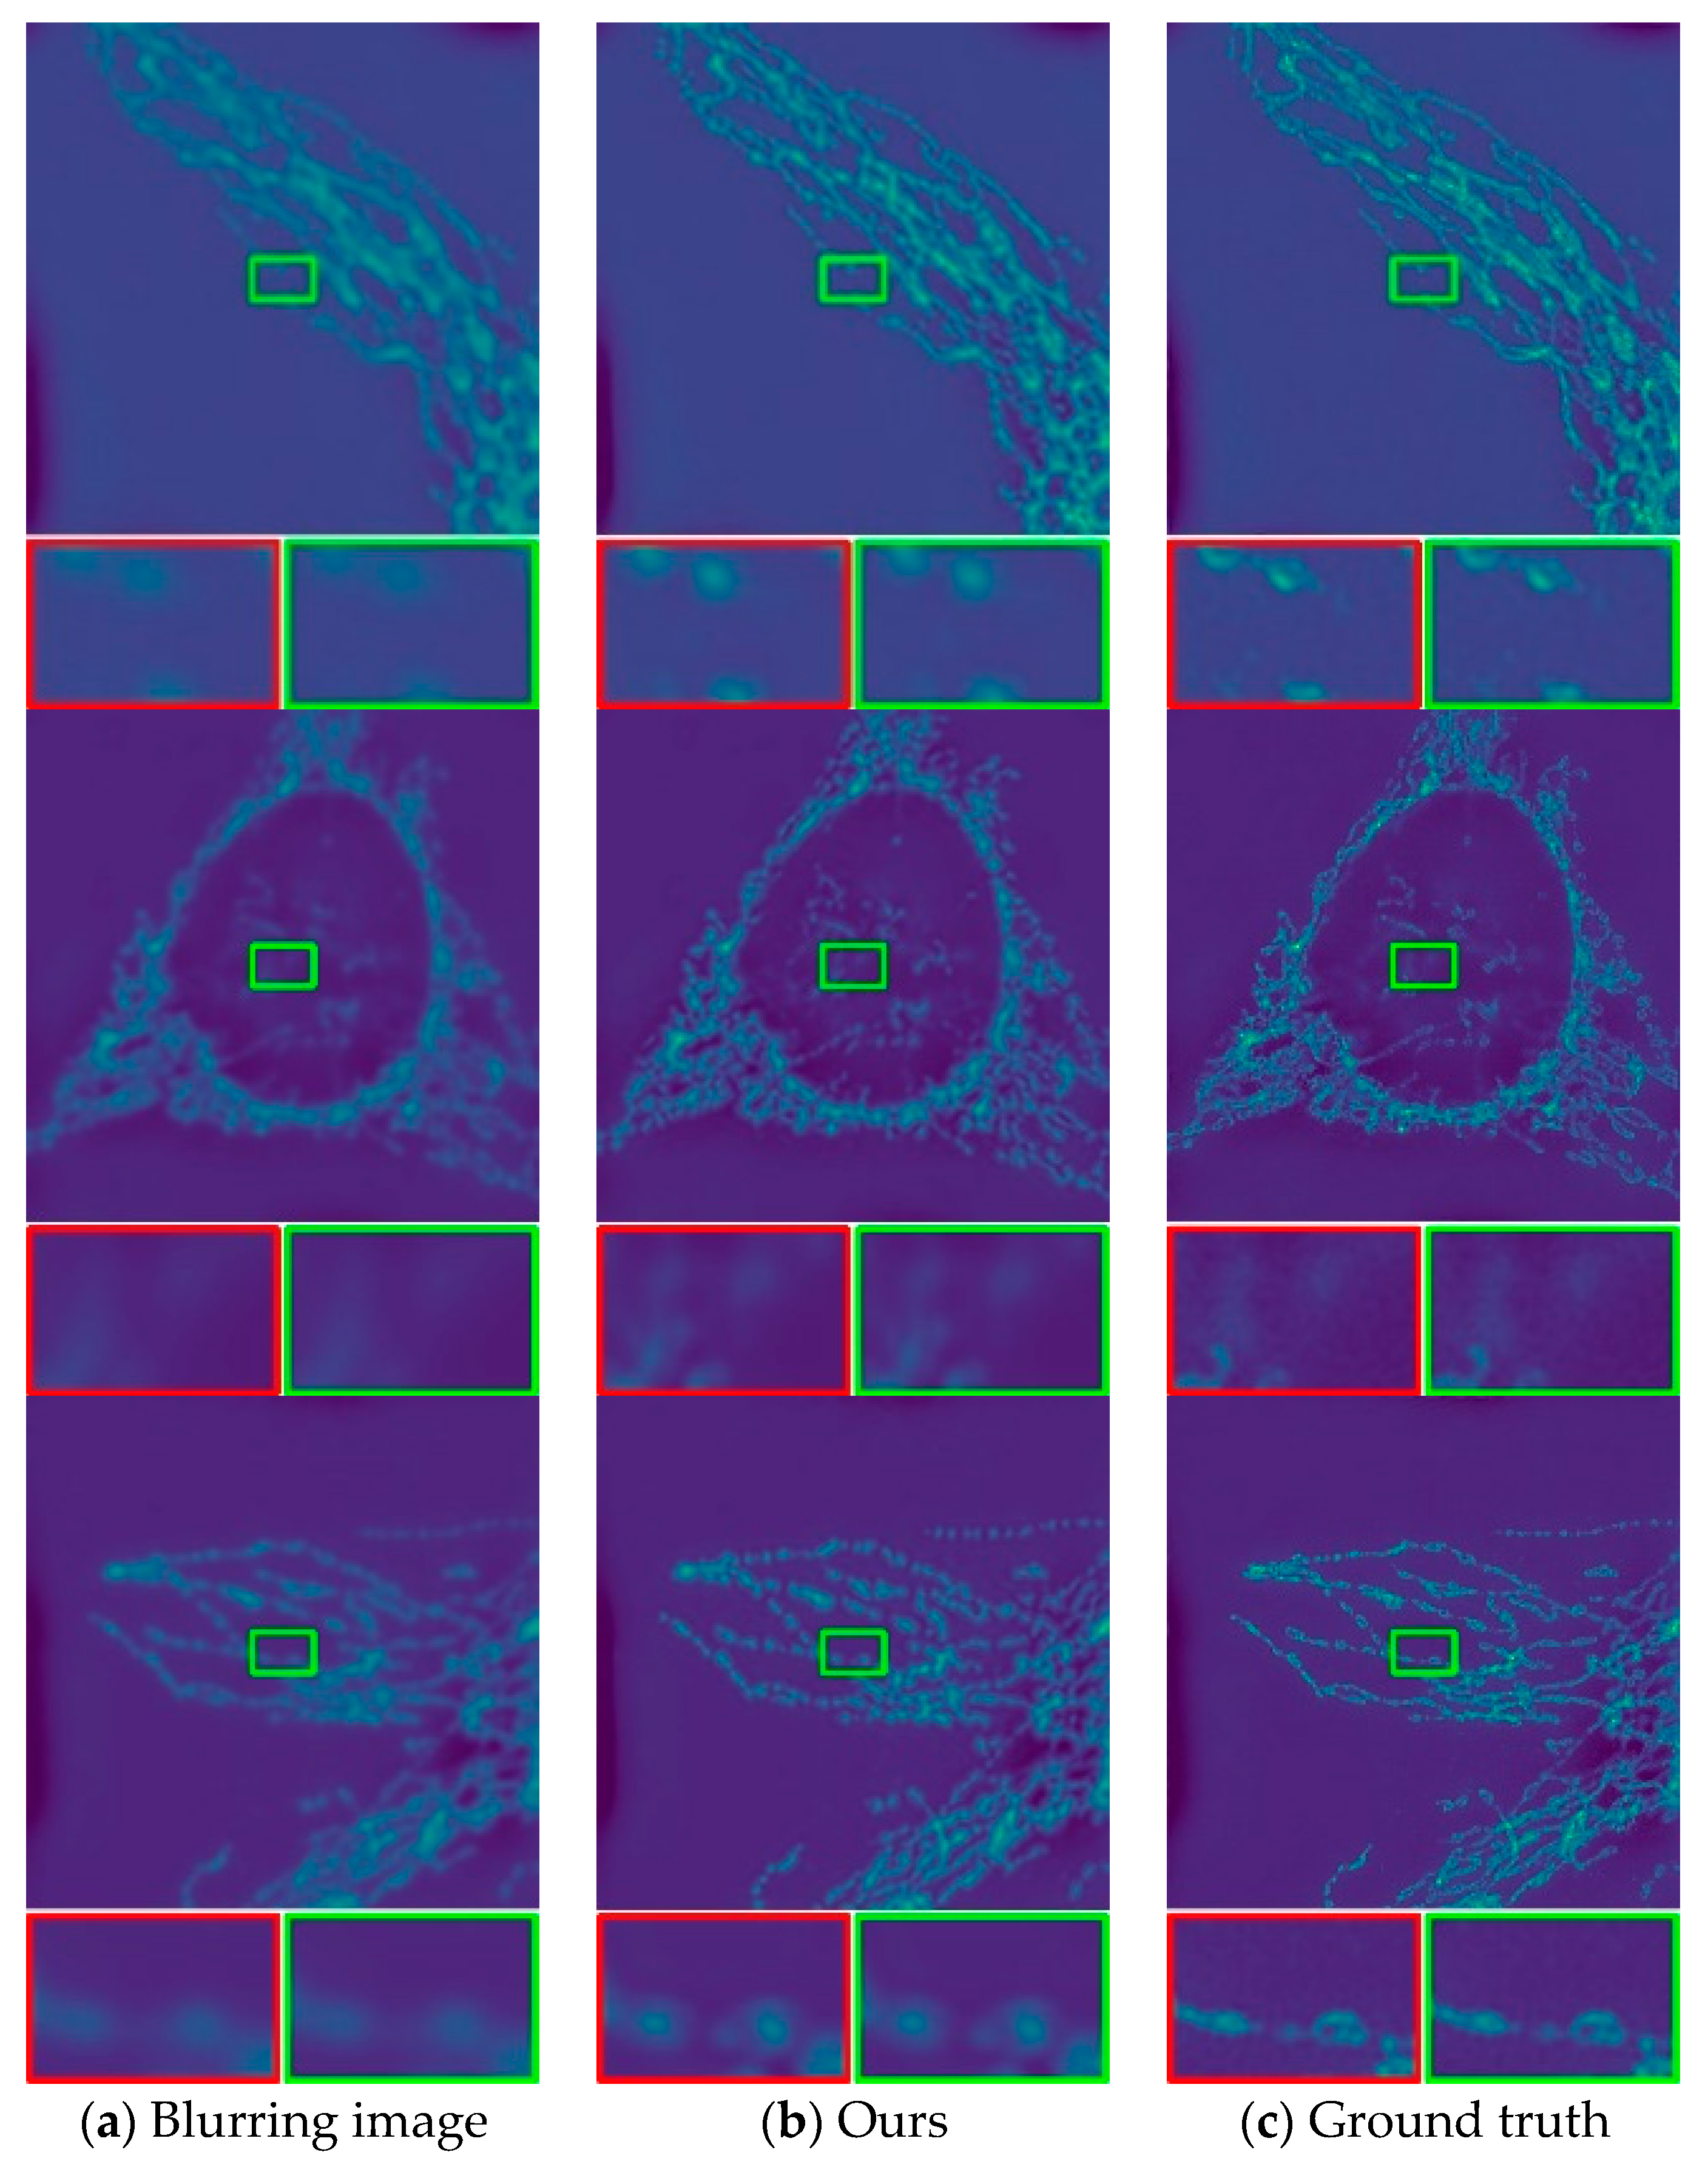

In this work, we evaluate the deblurring method on a real-world dataset. The objective is to assess the effectiveness of the proposed method for deblurring real-world images. We download the fluorescence microscopy dataset W2S. Here we directly use the best model generated by the training to test. The W2S dataset has ground-truth images and is therefore highly representative and persuasive in evaluating our proposed method. We evaluate 120 images from the W2S dataset to ensure a balanced representation of different imaging conditions, such as sample types and imaging methods. As is intuitively shown in the figure below, Figure 4 shows the partially deblurring W2S images resulting from the evaluated method. Figure 4 shows three processing effect diagrams. In each row, from left to right, there are input blurring images, optimization result images and ground truth images. Visual evaluation shows that the images recovered by our model are clearer and closer to reality than other models. From the perspective of objective quantitative indicators, we calculated the PSNR value and SSIM value of the 120 recovered images. The PSNR value is calculated using standardized formula and compared with the ground truth image. The SSIM value is commonly employed as a standard measure in the evaluation of image restoration techniques. We represent the results as a line chart in Figure 5. The PSNR value is represented by a blue line with circular markers. A higher PSNR indicates better image quality. In our dataset, PSNR values exhibit significant fluctuations. However, during specific epochs (such as the 24th, 65th, and 67th epochs), PSNR values reach notably high levels. The overall average PSNR value for the dataset is 29.643 dB. The SSIM value is depicted by a red line with “x” shaped markers, ranging from 0 to 1. Higher values indicate greater similarity between images. Similarly, SSIM values in our dataset show fluctuations, with certain epochs (like the 24th, 65th, and 67th epochs) displaying particularly high SSIM values. The average SSIM value for the entire dataset is 0.855. Quantitative analysis demonstrates that our method effectively improves the overall deblurring of W2S images.

Figure 4.

Deblurring results of the W2S: (a) the blurring image of the W2S; (b) the results of our method; (c) the ground truth of the W2S. The red and green framed portions are both locally enlarged images, allowing for a more intuitive comparison of image clarity by magnifying specific details.